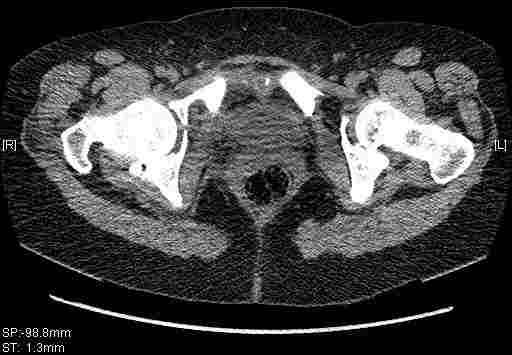

Женщина,58 лет, после ДТП 6 суток. Первично повреждение расценено как переломы ветвей лонной кости. После подтверждения повреждения вертлужной впадины,как чаще всего случается, вопрос встал о тактике. БОльшинство за консерватиное лечение.К сожалению кт у нас "во время" сломался. Прилагаю стандартные снимки вертлужки. У меня следующие вопросы к коллегам:1. Правильно ли рассценивать это повреждение как Т-образный перелом вертлужнй впадины?2. Можно ли добиться анатомической репозиции поверхности вертлужной впадины скелетным вытяжением в данном случае, если нет, что будет этому препятствовать?3. Если смещение останется таким как сейчас, через какое время появится необходимость эндопротезирования (по вашему опыту)?Спасибо.

Удалось сегодня вывести пациентку в соседнюю больницу, где есть кт. Срезы сделаны только горизонтальные.

|